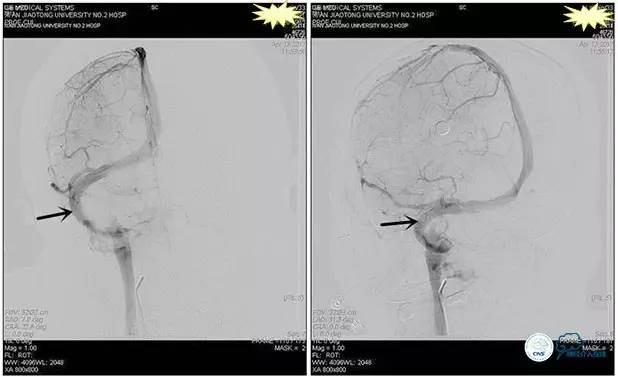

术后造影

术毕远近端压力差为:0

1、6mm×20mmAviator球囊(Cordis)分段对狭窄部位进行扩张。

2、植入7mm×40mmPrecise自膨支架。